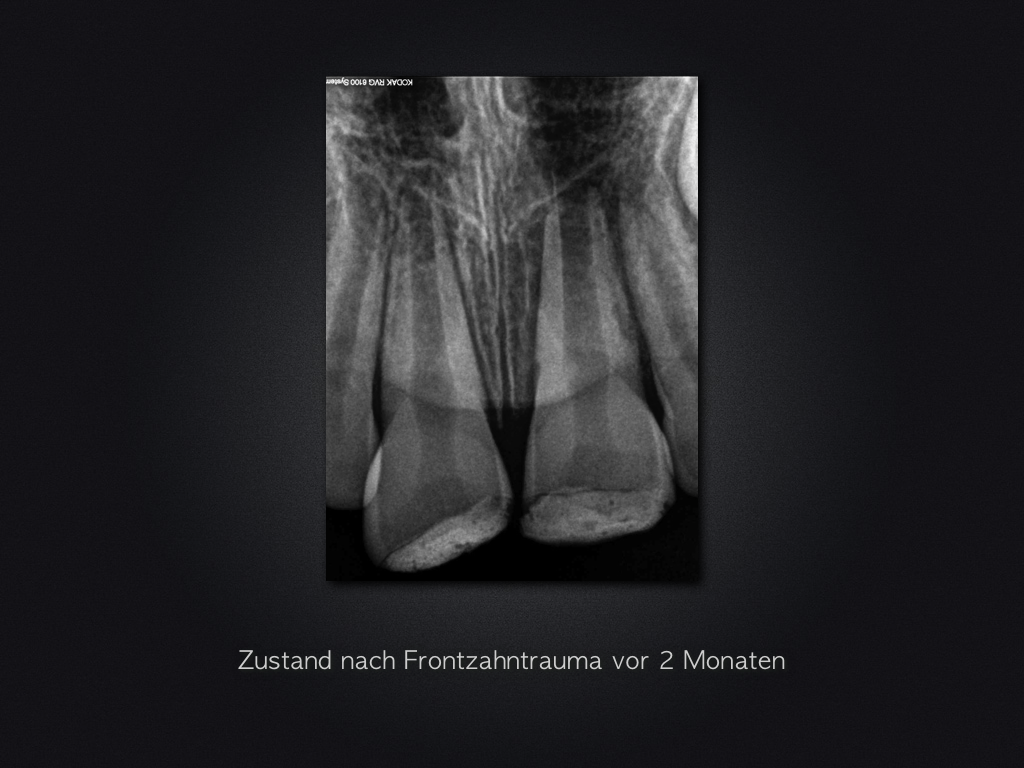

Revitalisierung – Recall nach 5,5 Jahren